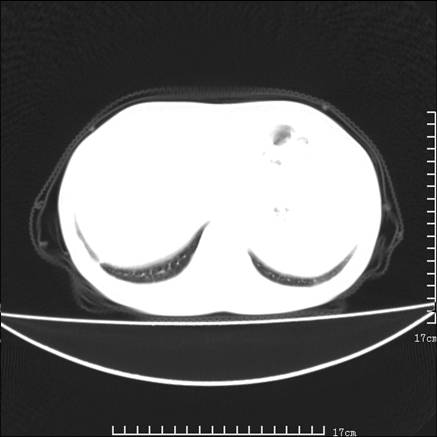

女,46岁,患胃溃疡多年,溃疡大小约1.0cm左右,后于5年前手术,病理为胃癌。主诉:半月前感冒后胸闷,气短,有咳嗽,无明显咳痰,无发热。偶有腰背部不适。

以下为高分辨扫描图像

双肺小叶间增厚,双肺散布粟米影和磨玻璃状影,以双肺上叶为重。结合病史考虑转移(癌性淋巴细管炎)可能性大。

结合病史:认为是典型肺部癌性淋巴管炎、淋巴结转移。请看图解。